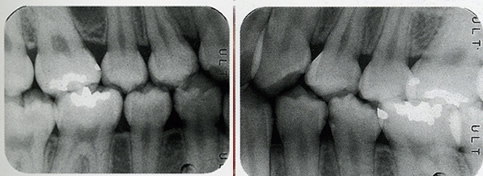

口腔内写真では、問題がなさそうに見えますが、バイトウイング(咬翼)法レントゲンを撮ったところ、歯の間に虫歯があることがわかりました。より早く異常を見つけることができました。

バイトウイング(咬翼)法で撮影したデンタルレントゲンです。